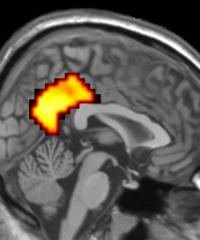

Though I haven't find a final say, My current RI involves analyzing the roles of amygdala, frontal cortex and mirror neuron networks in social cognition and emotion by utilizing various fMRI-based paradigms.I’m also interested in investigating the altered functional connectivity in patients with Neurological/Psychiatric disorders with Resting State fMRI analyzing techniques.